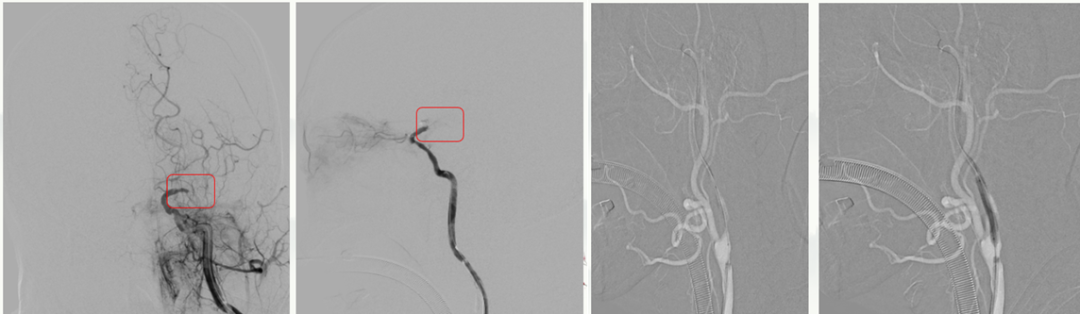

病历夹什么径技·第151期|串联营病历夹:京广连营_https://www.jmylbn.com_新闻资讯_第30张

病历夹什么径技·第151期|串联营病历夹:京广连营_https://www.jmylbn.com_新闻资讯_第31张

病历夹什么径技·第151期|串联营病历夹:京广连营_https://www.jmylbn.com_新闻资讯_第32张

病历夹什么径技·第151期|串联营病历夹:京广连营_https://www.jmylbn.com_新闻资讯_第33张

<<滑动查看下一张图片>>

• 术后即刻:去碘CT排除出血风险,梗死灶出现。

• 术后一天:DWI显示梗塞面积没有明显增大,MRA提示血管再通,发现存在LMCA动脉瘤。

• 术后四天:CT显示没有出血表现,梗死灶已经形成。

• 术后3个月:复查CT显示恢复情况良好。